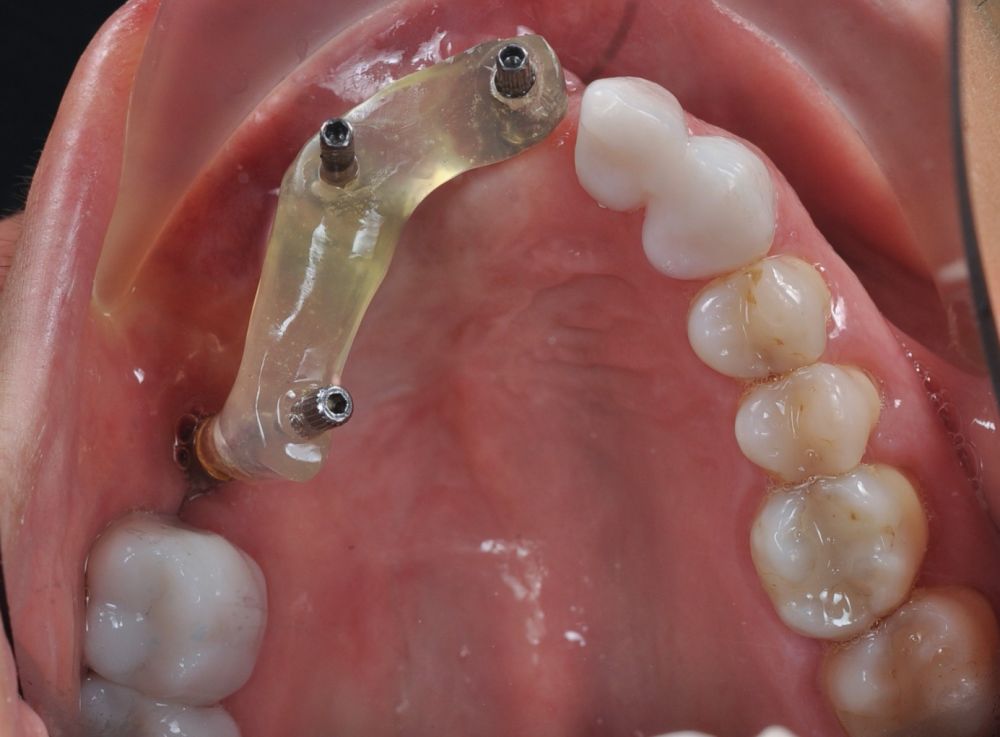

Para la fabricación de las estructuras, se eligió el óxido de zirconio monolítico como material restaurador sobre interfases metálicas en el puente implantosoportado, y coronas de óxido de zirconio monolítico en los dientes tallados previamente (1.7, 1.6, 2.2 y 2.3). Se tomaron impresiones de cubeta abierta con silicona de adición pesada y fluida (Zhermack Elite HD, Gmbh). Se realizó una prueba de pasividad analógica y el resto del proceso se confeccionó de manera digital, por lo que se hicieron pruebas estéticas de dientes impresas en 3D sobre interfases metálicas, para hacer todos los ajustes de función y estética previos al fresado del zirconio monolítico (Figuras 11, 12 y 13).

Las impresiones analógicas y el posterior flujo digital permitieron una correcta planificación protésica. Las estructuras definitivas, confeccionadas en óxido de zirconio monolítico sobre interfases metálicas de titanio, mostraron una adecuada adaptación pasiva tanto clínica como radiográficamente. La prueba estética permitió ajustes oclusales y funcionales mínimos, optimizando el resultado final.